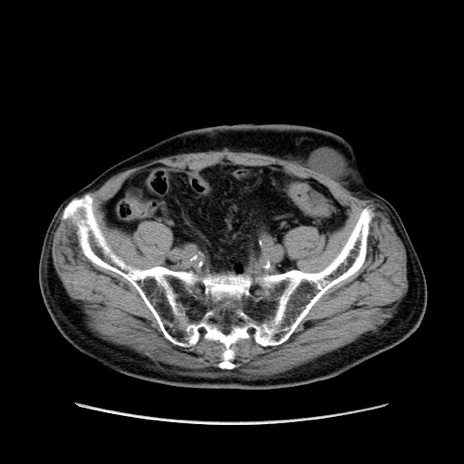

症例24(横断像)

【症例】80歳代男性

【主訴】左側腹部痛、嘔吐

【現病歴】本日早朝より左腹部に痛みあり。昼頃嘔吐認めたため、救急要請。

【既往歴】直腸癌(Mile手術)、胆摘

【身体所見】意識清明、BT 35.9℃、BP 221/93mmHg、SpO2 97%(RA) 、腹部:左ストーマ周囲に限局性の腹部膨隆あり。 膨隆部自発痛・圧痛あり・軟。

【データ】WBC 7700、CRP 0.09